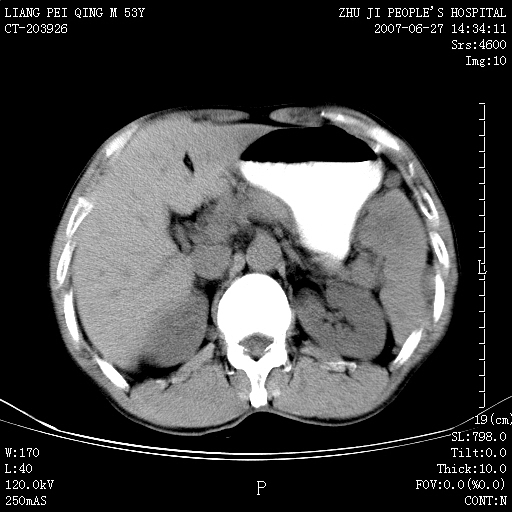

以下是引用余辉在2007-6-27 18:46:00的发言:[br]病灶多发,内可见大片状低密度区,病灶病灶等密度区轻度强化,动脉期后期病灶低密度区与高密度区对度增加,考虑1淋巴瘤2转移瘤3血管内皮细胞瘤(不知有否静脉期及延迟期扫描)

以下是引用zzzzhhhhaaaannnn在2007-6-27 20:44:00的发言:[br]脾脏 肋骨转移可能性大,下腔静脉内有癌栓

以下是引用狙击手在2007-6-28 10:35:00的发言:[br]1:定位:来源于脾脏。2:强化:强化,但不均匀。3:下腔静脉癌栓?下腔静脉充填不均匀与增强时间有关,延时即可明确。4:肋骨破坏?看起来并不确切。综上考虑几个最常见诊断:1;淋巴管瘤;2;血管内皮肉瘤(高度恶性,早期即可转移,常见肝,肺,骨)3;转移瘤(无特征性,只有肝或其它腹腔脏器有类似病变时,才可提示之)